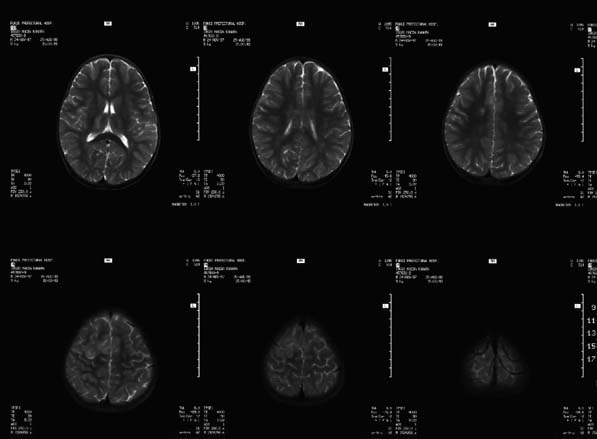

CaseHE02

- Age/Sex: 3 M

- Chief Complaint: けいれん発作重積状態

- Clinical Course:

- Lab. Data:

- Images:

- MR T1 (a)

- MR T1 (b)

- MR T2 (a)

- MR T2 (b)

- Tc-99m ECD Aug/27

- Tc-99m ECD Aug/31

あなたの診断は What

is your first impression?